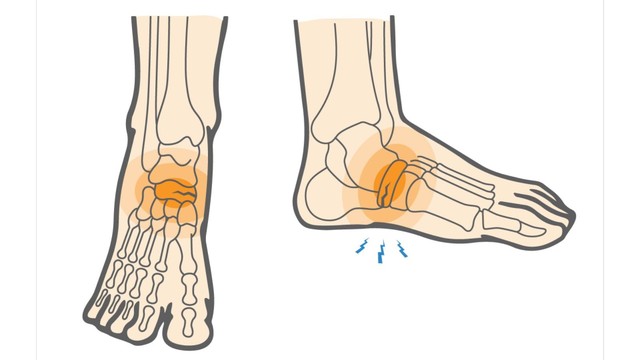

Rạn xương mắt cá chân bao lâu thì khỏi? Rạn xương mắt cá chân là một chấn thương phổ biến, thường gặp ở những người chơi thể thao, vận động viên hoặc người gặp tai nạn. Tình trạng này gây ra nhiều đau đớn, ảnh hưởng đến khả năng vận động và sinh hoạt của người bệnh.

Rạn xương mắt cá chân là một vấn đề y tế thường gặp khi xảy ra các tai nạn, bao gồm cả tai nạn giao thông và các tai nạn khác trong sinh hoạt hàng ngày. Xương cổ chân chịu áp lực lớn từ trọng lượng cơ thể và các hoạt động vận động, vì vậy khi bị tổn thương, nó có thể gây ra đau đớn, khó khăn trong việc di chuyển và ảnh hưởng đến chất lượng cuộc sống của người bệnh.